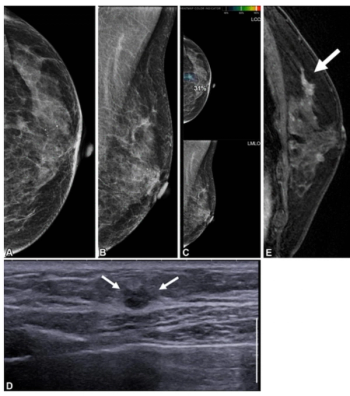

Cardiac CT angiography may provide insights on common post-op complications of left atrial appendage closure, ranging from peri-device leaks to device-related thrombus, according to research presented at the American Roentgen Ray Society (ARRS) conference.